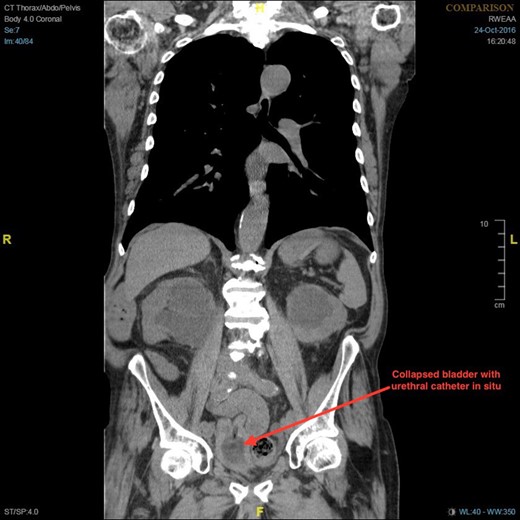

Coronal section of CT demonstrating bilateral hydronephrosis and collapsed bladder with urethral catheter in situ.